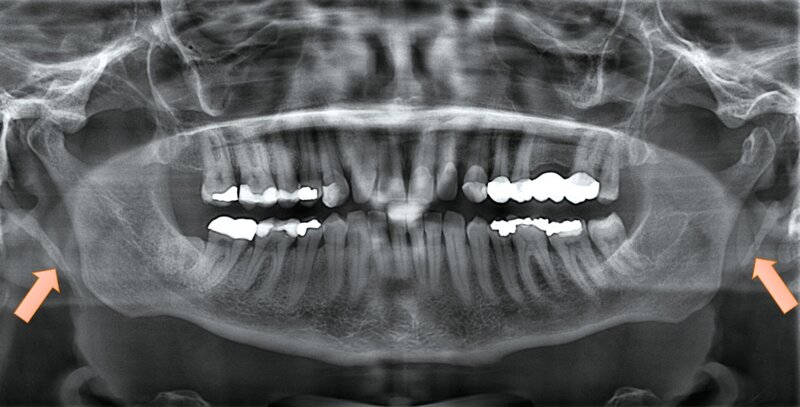

Eine 49-jährige Patientin stellte sich vor, nachdem ihr Hauszahnarzt im Rahmen einer Routineuntersuchung ein Orthopantomogramm (OPG) angefertigt hatte. Dabei war zufällig eine beidseitige Verlängerung des Processus styloideus aufgefallen, dabei auf der rechten Seite deutlich ausgeprägter (Abbildung 1).

Die klinische Untersuchung ergab keine Hinweise auf Sensibilitätsstörungen, eine Fazialisparese oder Hirnnervenausfälle. Allerdings war die Palpation des rechten Kieferwinkels schmerzhaft, insbesondere bei der intraoralen Untersuchung der Tonsillenloge. Eine mechanische Provokation durch Kopfdrehung und Palpation verstärkte die Beschwerden. Die prothetisch versorgten Zähne zeigten keine pathologischen Befunde. Zur weiteren Diagnostik wurde eine Digitale Volumentomografie (DVT) mit 3D-Rekonstruktion durchgeführt. Diese bestätigte die im OPG vermutete Diagnose eines beidseitig elongierten Processus styloideus, mit einer stärkeren Ausprägung auf der rechten Seite (Abbildung 2).

Die Diagnostik des Eagle-Syndroms basiert auf einer Kombination aus Anamnese, klinischer Untersuchung und bildgebenden Verfahren. Als Erstuntersuchung ist ein OPG geeignet, liefert jedoch keine detaillierten Informationen über die räumliche Lage des verlängerten Processus styloideus. Daher gilt die dreidimensionale Bildgebung (CT oder DVT) als Goldstandard, um die exakte Länge und die Beziehung zu den angrenzenden Strukturen zu bestimmen [Mortellaro et al., 2002]. Differenzialdiagnostisch müssen Kiefergelenkpathologien, eine Trigeminusneuralgie und psychosomatische Ursachen ausgeschlossen werden, was jedoch durch eine bildgebende Diagnostik zuverlässig möglich ist [Kozakovičová et al., 2023].